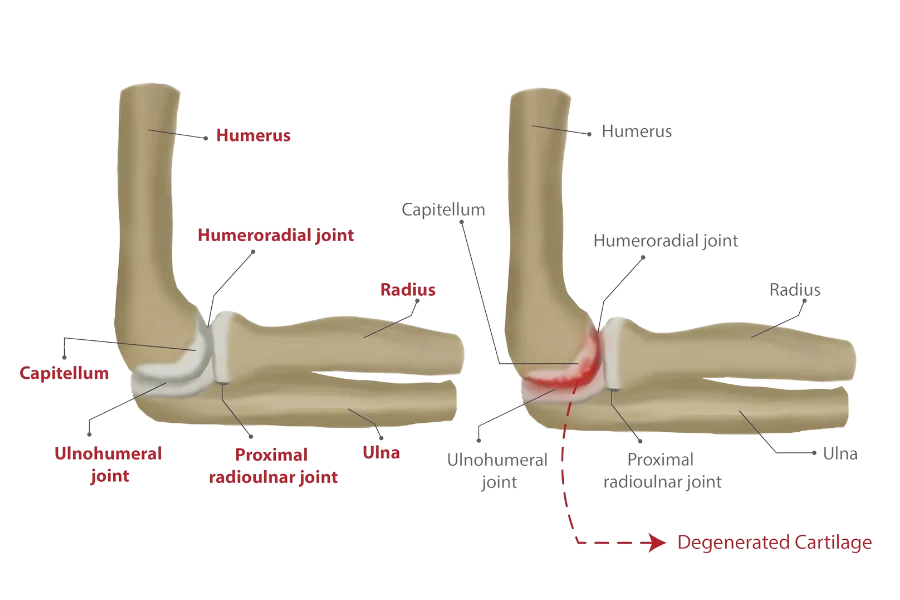

When the cartilage in the elbow becomes worn or injured, elbow arthritis develops. Overuse due to ageing and repetitive activities, as well as injury, such as a fracture or dislocation, can cause damage.

When the cartilage in the elbow becomes worn or injured, elbow arthritis develops. Overuse due to ageing and repetitive activities, as well as injury, such as a fracture or dislocation, can cause damage.